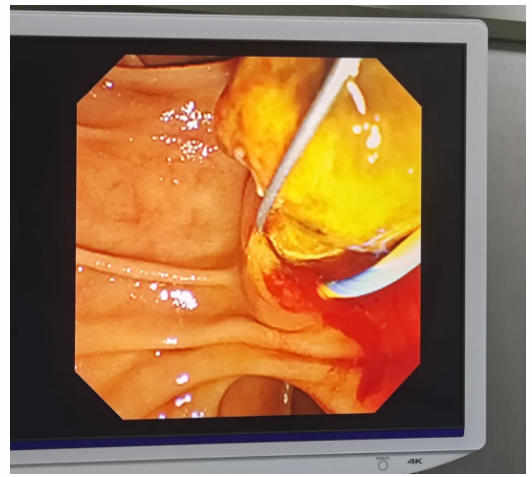

病情就是命令!患者抱着一线希望转入脾胃肝胆内科。脾胃肝胆内科执行主任詹原泉带领团队进行了全面评估,深知这是一场必须打赢的硬仗。基于我们在复杂ERCP领域深厚的技术积淀,以及詹原泉主任多次成功为高龄、高危患者突破手术禁忌的丰富经验,我们果断决策:为了即刻解除患者难以忍受的剧痛,避免更严重的并发症,必须迎难而上!经过科室内部严谨周密的术前讨论和万全准备,詹原泉主任亲自操刀,凭借炉火纯青的内镜操作技术,成功为患者实施了ERCP+胆总管取石术。手术过程顺利,困扰患者多时的结石被顺利取出,剧痛根源被一举清除!患者术后安全转入普通病房。